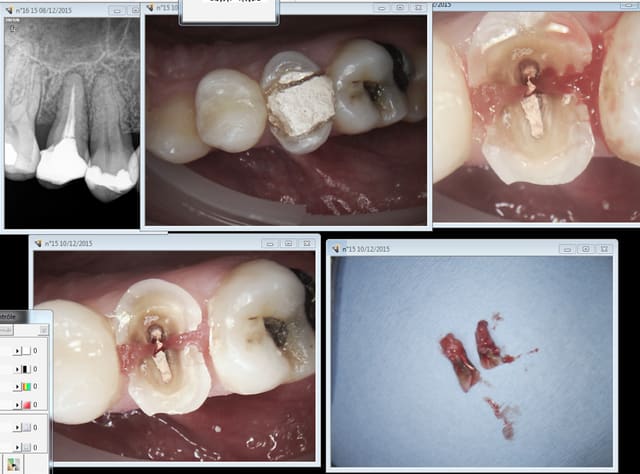

chicot29

10/12/2015 à 15h29

Sinon tu les revois quelque temps après. Endo extraction. pas rentable. -)))

Bon là j'ai pas trop perdu c'est pas moi qui ai fait l'endo, chiotte un ic-coiffe en moins 33 ,74 euros au lieu de 667 ca fait un trou dans le CA. -))))

Capture d e cran 2015 12 10 14.28 - Eugenol